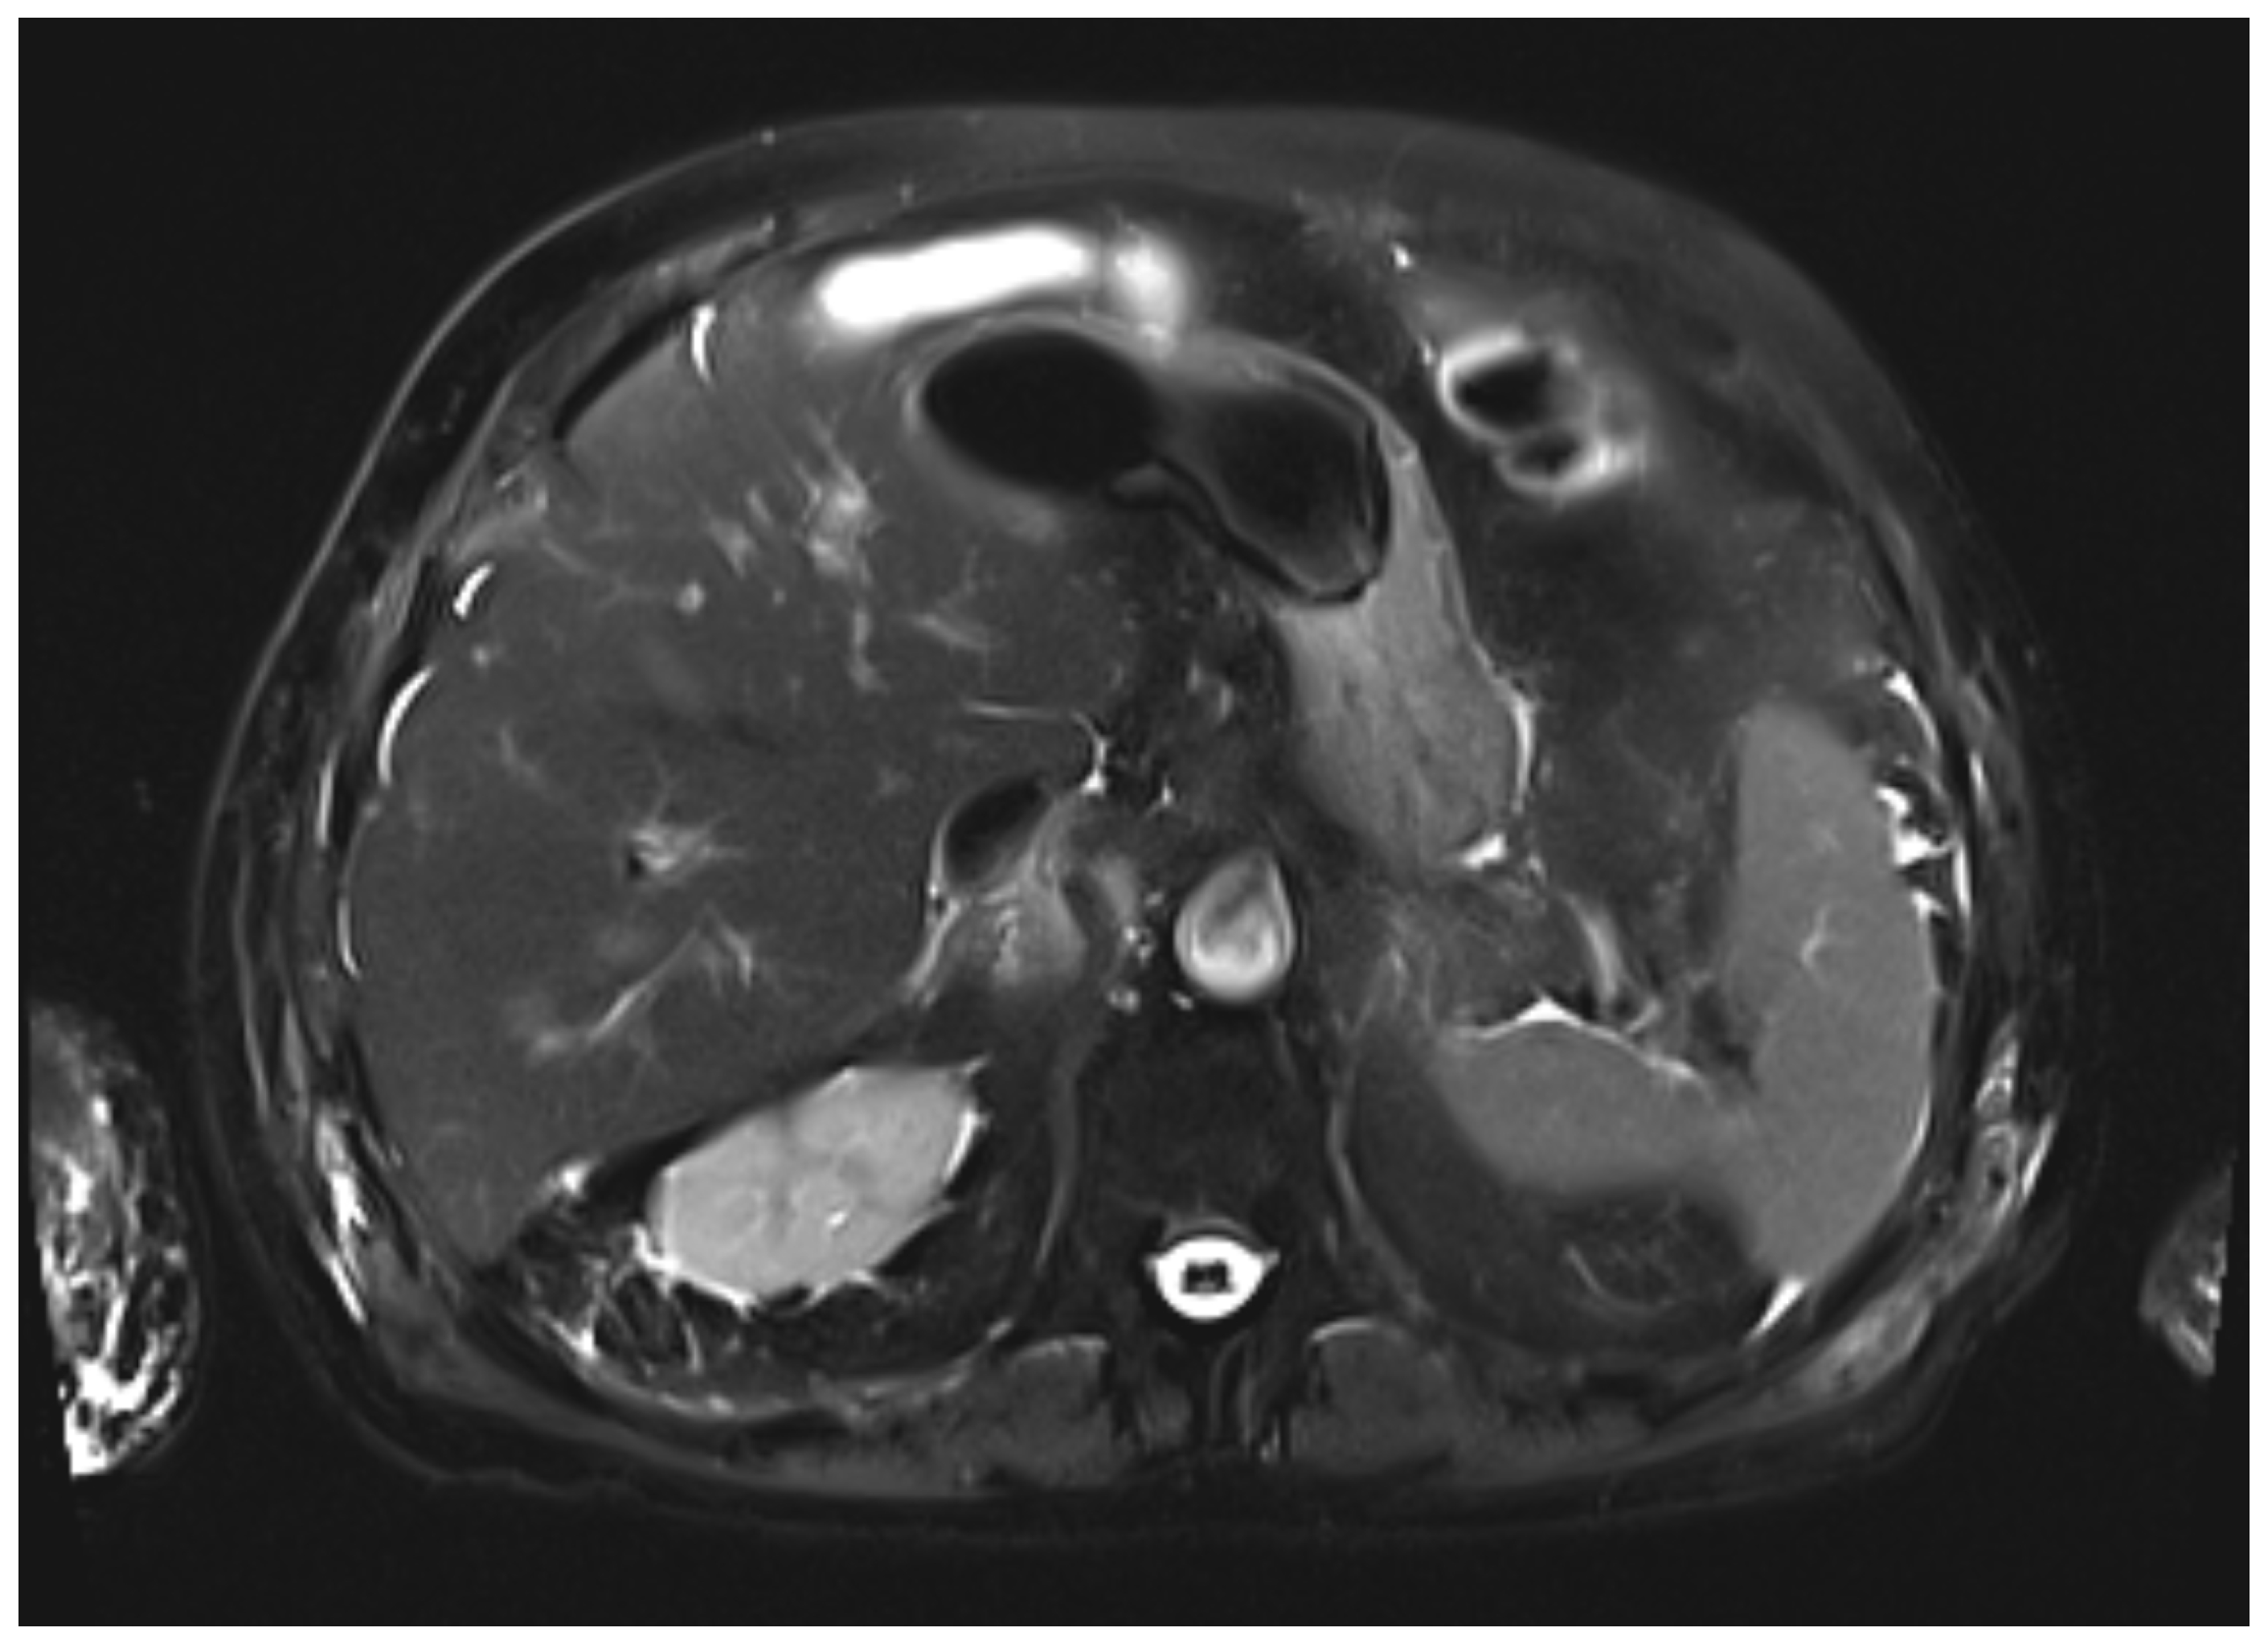

During the first days of mycophenolate therapy, a transient biochemical flare was observed (20 August 2025), with total bilirubin peaking at 4.7 mg/dL (direct 3.7 mg/dL), ALP 214 U/L, and GGT 1195 U/L. A magnetic resonance cholangiopancreatography performed the same day showed normal intrahepatic and extrahepatic bile ducts with no obstruction (Figure 3 and Figure 4). Over the following week, a partial biochemical improvement occurred (27 August 2025): ALT 222 U/L, AST 96 U/L, ALP 481 U/L, GGT 1758 U/L, total bilirubin 1.9 mg/dL.

Figure 4. Axial T2-weighted HASTE MR image. The liver parenchyma shows homogeneous signal intensity, without focal lesions or signs of cholestasis.